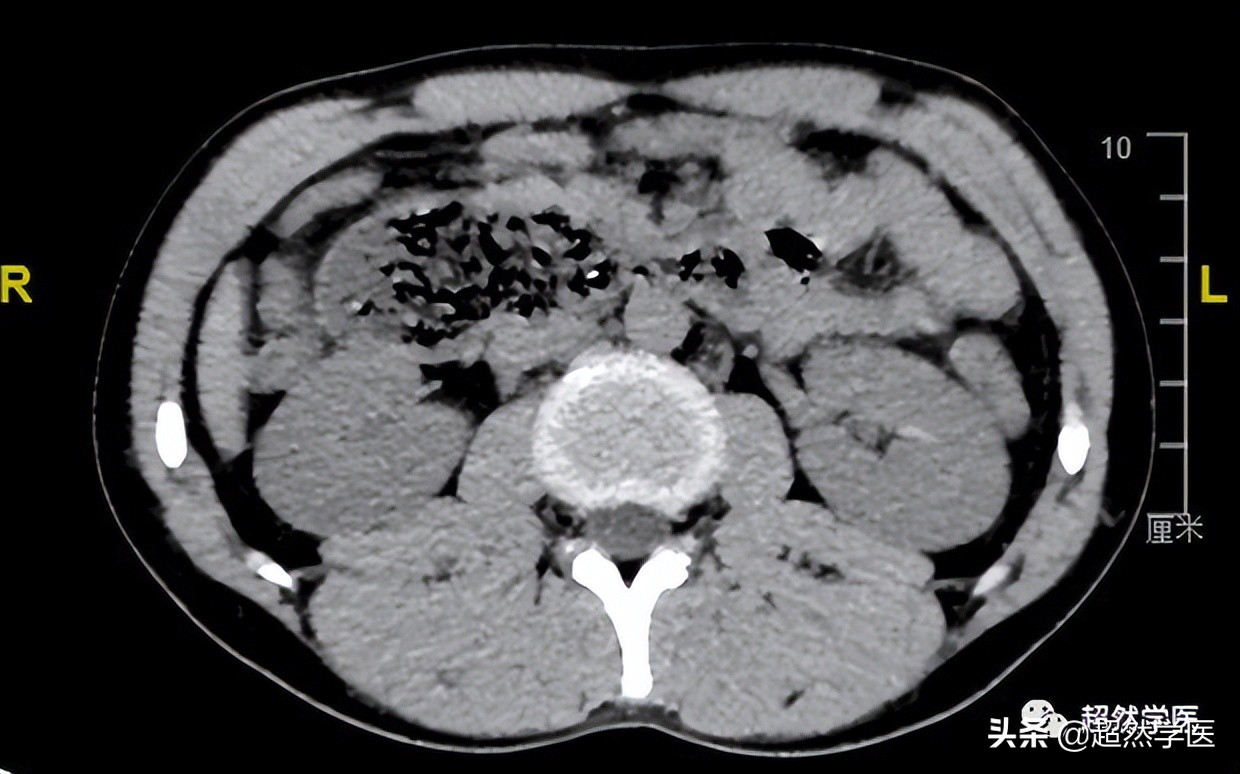

腹部CT的影像非常典型:

十二指肠近端扩张明显,而中间部分极为狭窄,约0.5cm左右

胃腔大量胃液。没有明显的胃肠型体征和其他部位的梗阻或结石征象。